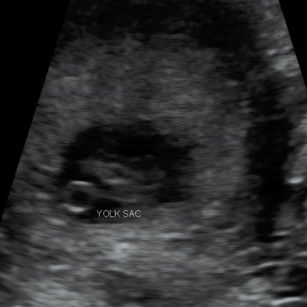

Tell Me About My Baby!

Size: ~0.6 inch (1.6 cm), the size of a Raspberry!

Development Highlights:

Baby is now called a fetus instead of an embryo.

Fingers and toes are forming, though webbed.

Facial features more defined: ears, eyelids, and nose.

Heart has four chambers and beats regularly.

8 Weeks Pregnant